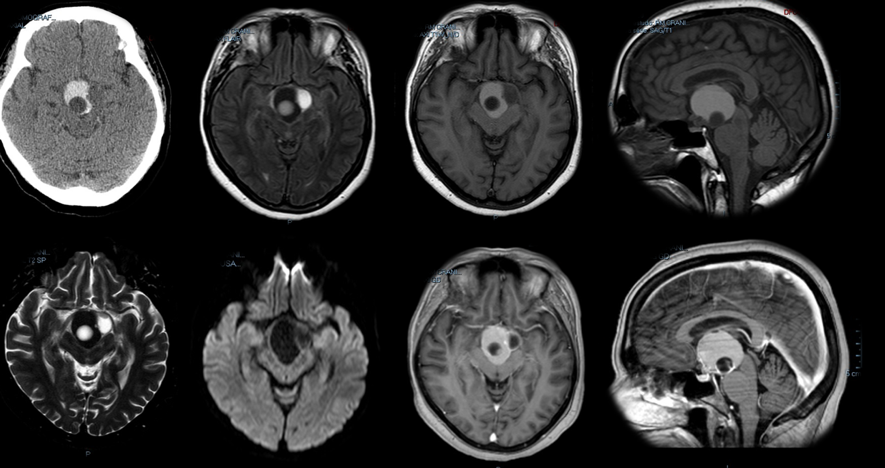

2. Exames de Imagem – Essenciais

Ressonância Magnética (RM) – Exame de Escolha

Padrão-ouro para diagnóstico

Características Típicas na RM:

• Localização: região selar/supraselar

• Componente cístico: presente em 70-75%

• Conteúdo hiperintenso em T1 (líquido proteináceo)

• Componente sólido: com realce heterogêneo

• Calcificações: 80-87% (melhor vistas na TC)

• Relação com estruturas adjacentes:

• Compressão do quiasma óptico

• Envolvimento hipotalâmico

• Relação com haste hipofisária

• Extensão ventricular

RM com Contraste (Gadolínio):

• Essencial para delinear o tumor

• Avaliar componentes sólidos e císticos

• Planejamento cirúrgico

Tomografia Computadorizada (TC)

Complementa a RM

Indicações:

• Melhor para identificar calcificações

• Avaliar estrutura óssea da sela

• Quando RM não disponível

Achados Típicos:

• Calcificações: 90% em crianças, 50% em adultos

• Lesão cística hipodensa

• Componente sólido com realce